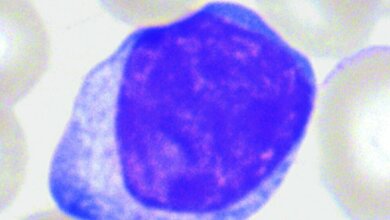

Non-Hodgkin-Lymphome (NHL) stellen keine einheitliche Erkrankung dar. Sie bilden eine äußerst komplexe Gruppe von Krebserkrankungen, die von Zellen des lymphatischen Systems ausgehen. NHL gehören zu den bösartigen Erkrankungen des Lymphgewebes und stellen die vierthäufigste Krebsform im Kindes- und Jugendalter dar. NHL entstehen durch Veränderungen im Erbgut der für die Immunabwehr wichtigen Lymphozyten. Meist sind die Lymphknoten betroffen, in fortgeschrittenen Krankheitsstadien können aber auch Knochenmark, Lunge, Leber und Milz befallen sein. Die Erkrankung beginnt typischerweise mit einer schmerzlosen Lymphknotenschwellung, die im weiteren Verlauf auch Bauchschmerzen oder Atembeschwerden auslösen kann, außerdem Fieber, Gewichtsverlust, Nachtschweiß und Müdigkeit. Mehr als 30 Untergruppen sind bekannt. Zwar liegt die langfristige Überlebensrate zwischen 70 und 90 Prozent. Bei einem Rückfall ist die Aussicht auf Heilung insgesamt aber eher schlecht.